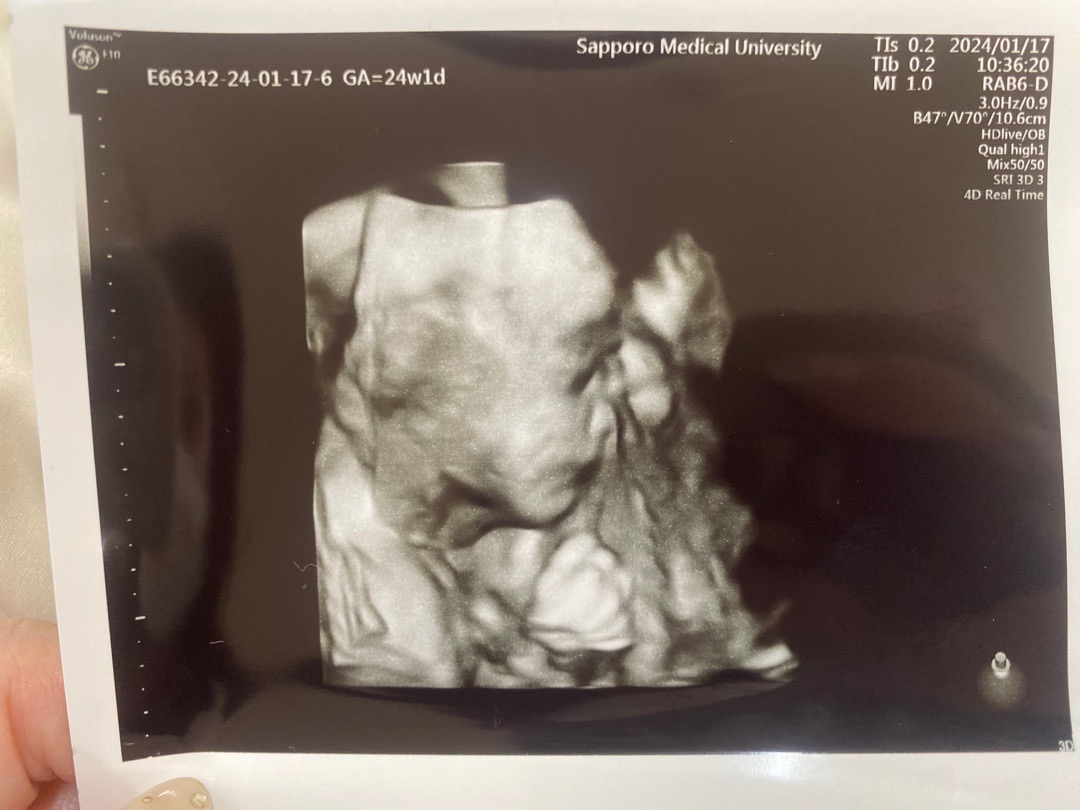

横顔24w

なかなか正面見てくれず🥹

こんなふうに横からも見えるんですねっ😲😲

横顔のエコー写真は逆に珍しい🥹✨ぎゅっと握ってるこぶしが可愛いです🤜🏻💖